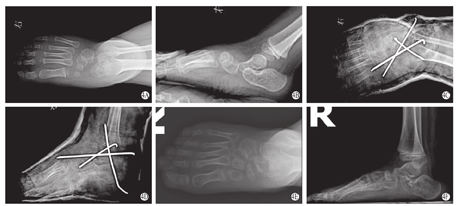

术后6个月内2例(4足)出现畸形复发(表现为负重站立侧位X片距舟关节向背侧半脱位),其中1例(2足)伴有多关节挛缩症,1例(2足)伴有痉挛性脑瘫,再次给予反式Ponseti石膏矫形,距舟关节切开复位后畸形矫正。其余患儿无伤口感染、距骨坏死等并发症。典型病例术前和末次随访外观见图2、图3。

末次随访时,11例(18足)中Adelaar评分为优2足(11.1%),良15足(83.3%),中1足(5.6%),优良率达94.4%(17/18)。仅1足因年龄较大(31.2个月)足的重塑型能力有限,畸形严重而松解范围与其他足相比稍大,术后评分较低。